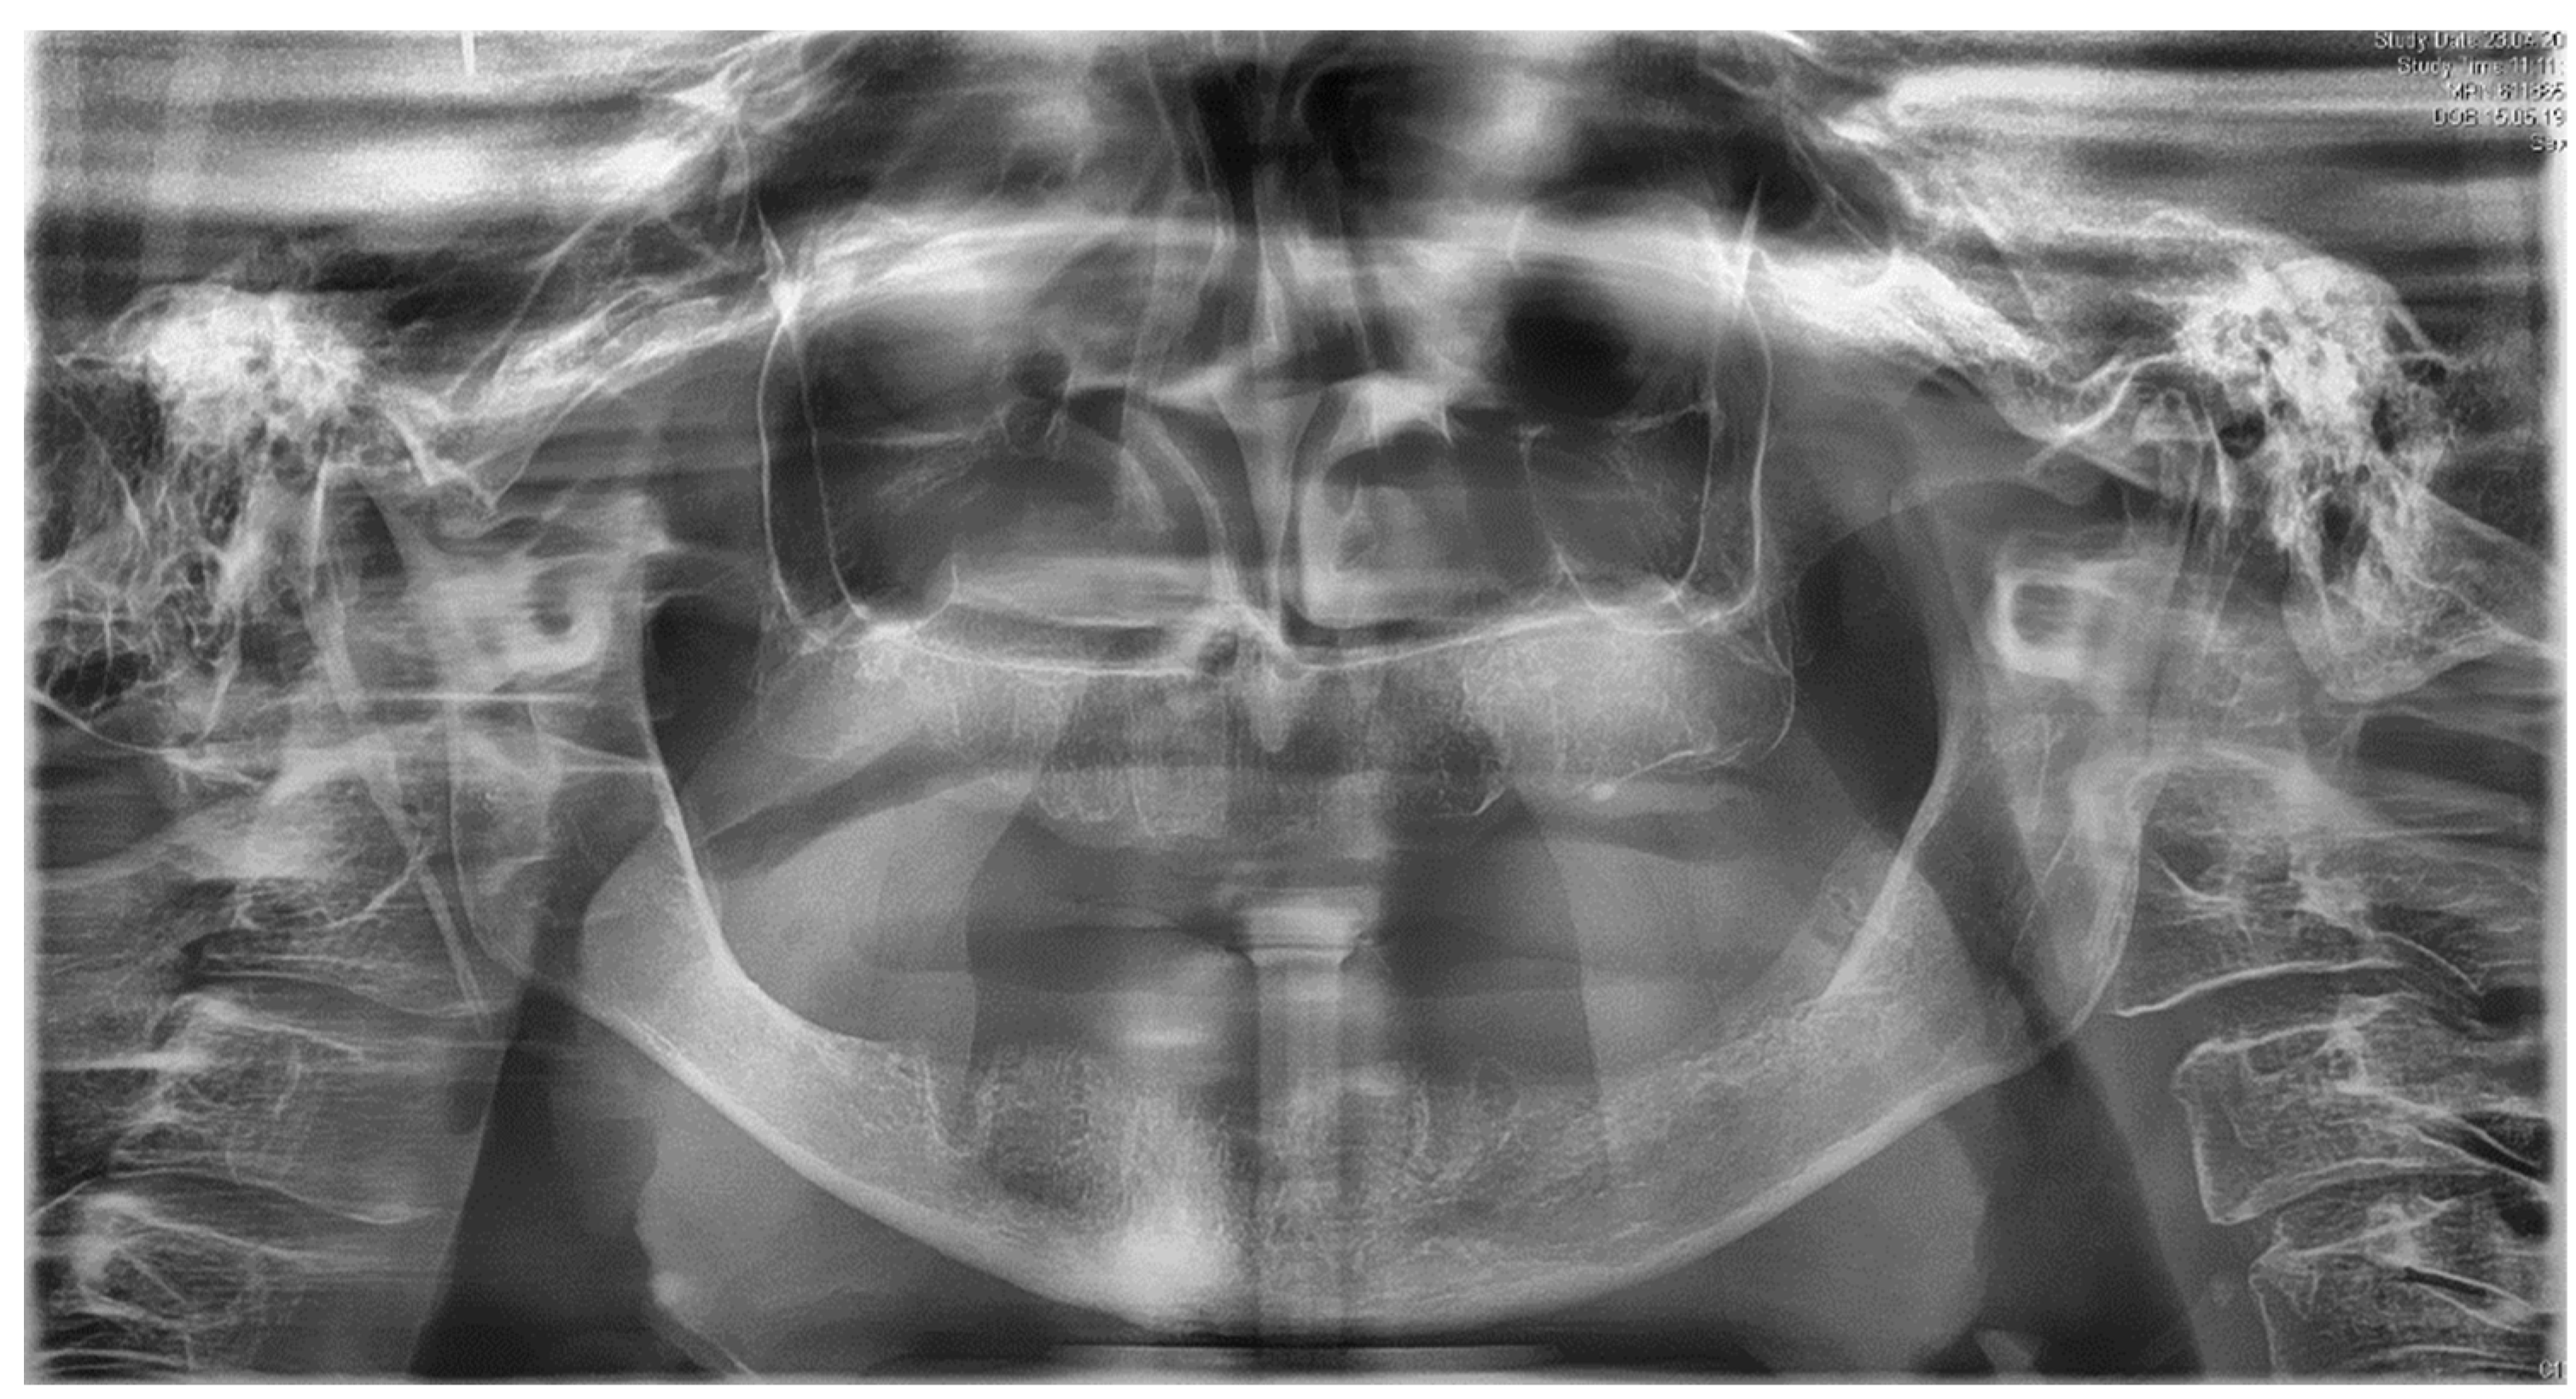

2. Case Report